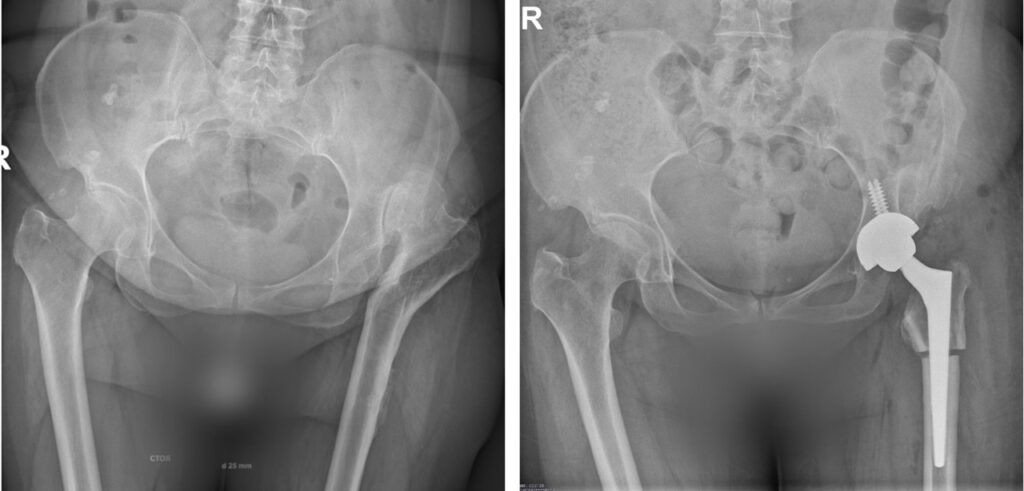

Обследования выявили не только врождённый вывих левой бедренной кости, но и левосторонний диспластический коксартроз 3 стадии, подвздошно-бедренный неоартроз слева и приобретённую деформацию проксимального отдела бедра (с укорочением левой ноги на 2 см). Пациентка обратилась на консультативный приём к д.м.н., врачу-травматологу-ортопеду Новосибирского НИИТО им. Я.Л. Цивьяна Минздрава России Александру Пронских.

Эксперт объясняет, что укорочение левой ноги сохранилось, поскольку головка левого тазобедренного сустава осталась в положении вывиха. Однако показанием для хирургического лечения является не само укорочение, а сформировавшиеся с возрастом явления артрита, сопровождающиеся сильными болями и деформацией.

Ортопедам удалось выровнять длину ног, нормализовать биомеханику тазобедренного сустава, восстановить опороспособность и устранить болевой синдром

«Укорочение, ранее выполненные операции, многоплоскостная деформация проксимального отдела бедренной кости относят это вмешательство в разряд первичного сложного эндопротезирования тазобедренного сустава. Однако изменённая анатомия не позволяла имплантировать эндопротез, что потребовало повторной остеотомии бедренной кости для восстановления её нормальной анатомической оси.

Хирургическое вмешательство прошло штатно. Мы восстановили правильный центр вращения сустава за счёт низведения бедра, исправили ось бедренной кости за счёт повторной остеотомии в зоне деформации. Это позволило выровнять длину ног, нормализовать биомеханику тазобедренного сустава, восстановить опороспособность и устранить болевой синдром», — комментирует Олег Голенков.